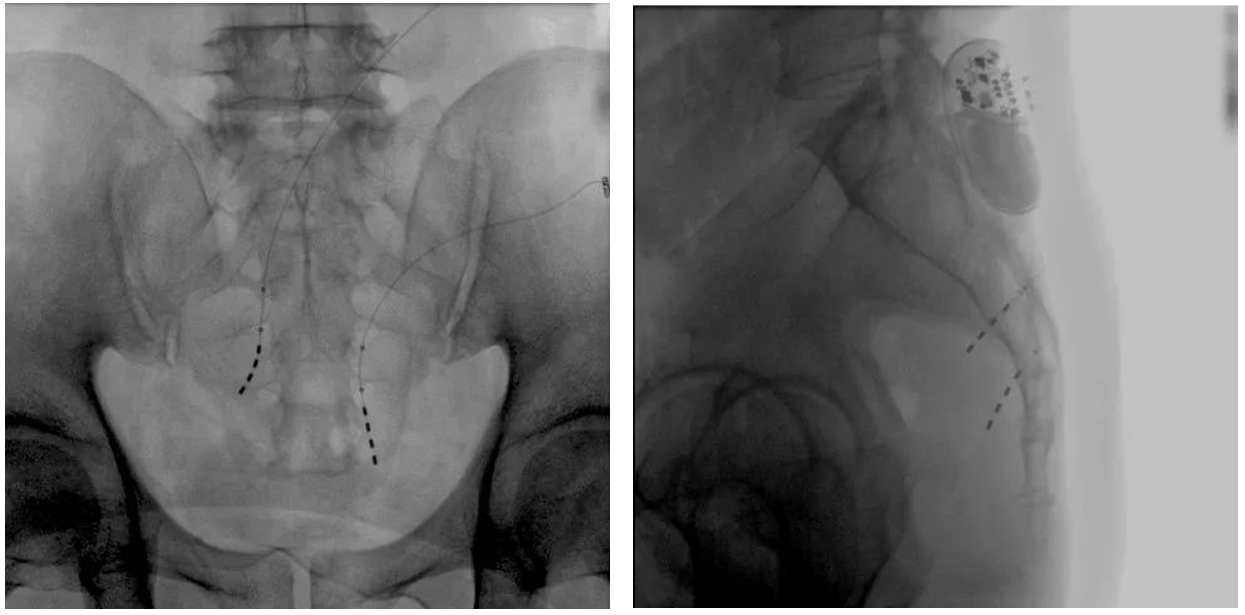

患者術(shù)前影像

大平板一體式移動C形臂術(shù)中影像

在骶神經(jīng)調(diào)控術(shù)或者骶神經(jīng)刺激術(shù)(SNS)中,醫(yī)師首先會在透視引導(dǎo)下把電極通過導(dǎo)針插入到骶3神經(jīng)孔位置,通過脈沖電流的刺激,達到興奮神經(jīng)纖維并抑制逼尿肌收縮。在這一步,醫(yī)師會先對患者的神經(jīng)刺激反應(yīng)做測試評估,如果刺激效果明顯,說明該方案能夠達到手術(shù)預(yù)期。接下來醫(yī)師會在附近皮下脂肪處植入一塊脈沖電流發(fā)生器并與電極相連,使該部位今后能得到長期的電刺激,改善OAB癥狀。

? 相較于影增C形臂,平板探測器成像的畸變更少,能夠準(zhǔn)確體現(xiàn)電極和骶孔位置關(guān)系,提高手術(shù)效果預(yù)期。